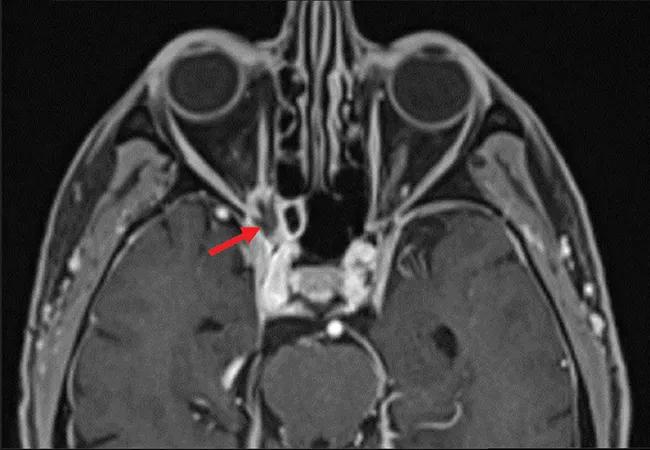

Brain MRI revealed an irregularly shaped lesion with peripheral enhancement and a central nonenhancing region just inferior to the right optic nerve at the orbital apex (Figure 2). It was thought that this finding might represent a small abscess or area of necrosis. Scattered paranasal sinus mucosal thickening and increasing asymmetric enlargement of the right anterior cavernous sinus relative to previous images were also noted.

Figure 2. Magnetic resonance imaging of the orbit showed lesions (arrows) in axial T1-weighted fat-suppressed series (A) and coronal multiplanar reformation (B) views.